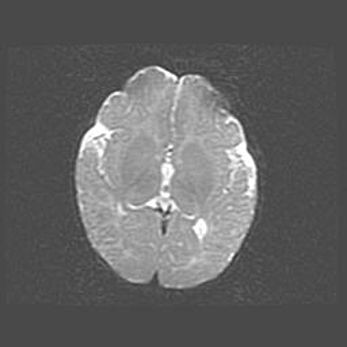

Сообщающаяся гидроцефалия. Кистозная энцефаломаляция головного мозга.

Возраст: 3 месяца 4 дня

Вес: 3100 г

Пол: женский

Окружность головы: 34 см

Срок гестации: 31 неделя

Кистозная энцефаломаляция головного мозга - одна из форм поражения головного мозга в детском возрасте. Характеризуется возникновением множественных и распространённых кист в коре, белом веществе и подкорковых образованиях головного мозга у плодов, новорождённых и детей раннего возраста. Развитие кистозной энцефаломаляции связано с внутриутробной асфиксией и гипотонией, родовой травмой, тромбозом синусов, пороками развития сосудов, инфекциями, сепсисом и другими причинами. Наиболее значимые инфекционные агенты: вирусы простого герпеса, цитомегалии, краснухи, токсоплазмы, энтеробактерии, золотистый стафилококк и другие.